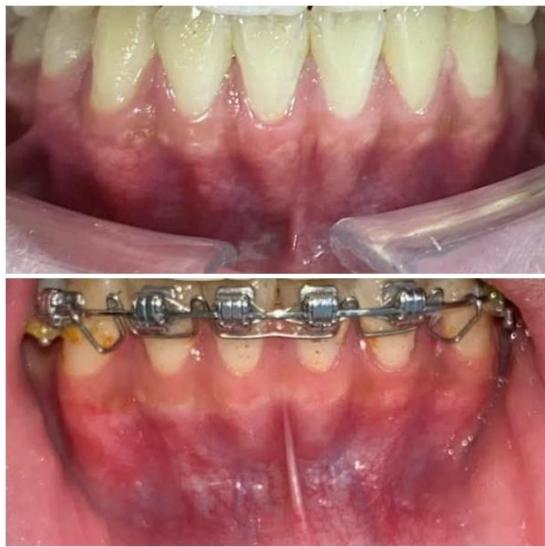

### b) Intraoral Examination

Intraoral examination revealed severe proclination and protrusion of both the maxillary and mandibular incisors [6]. The occlusal relationship was Class I at the canine (tooth 3) and first molar (tooth 6) levels bilaterally. A critical unfavorable biological factor was the proximity of the mandibular incisor roots to the labial cortical plate, representing a high-risk condition when planning extraction-based anterior retraction mechanics [10-12]. All four third molars were present.

Figure 2: Pre-Treatment Intraoral Photographs